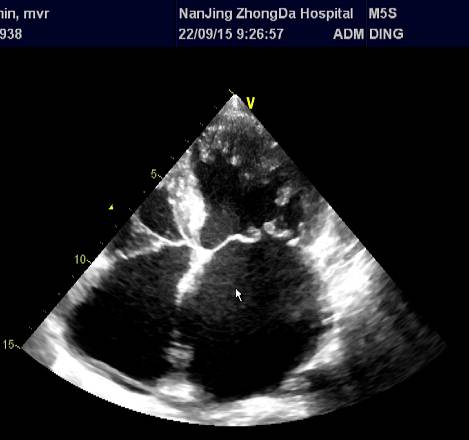

\u000b心超(2015-09-22):二尖瓣前叶脱垂伴中度关闭不全、主动脉瓣钙化,LA(5.4)、RA(4.2)、LV(6.4)、 LVEF 0.40,三尖瓣中度、主动脉瓣中度返流、肺动脉高压(PG=36mmHg)、心功能减低 。